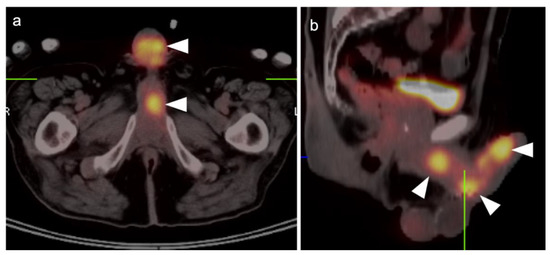

2.6. Vulvar Carcinoma